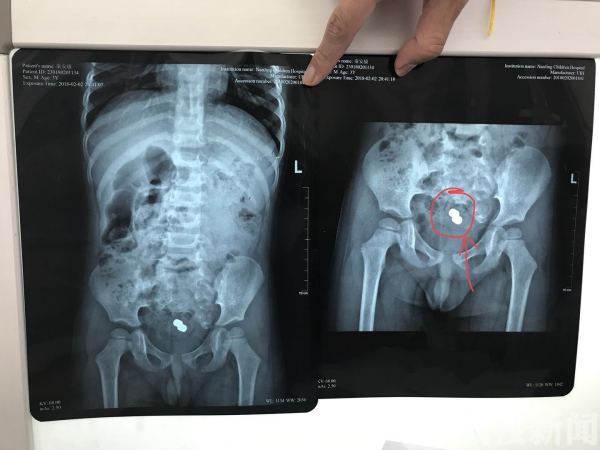

康康妈妈觉得塞入肛门也没有关系,说不定过两天解大便的时候解下来呢,于是就没有当回事情,还不停的给他吃东西,指望多点大便解下来。可是一连几天康康光吃东西,就是不解大便,肚子鼓鼓的,奶奶知道情况后,居然用手扣,不但没有扣出来,反而肛门口还出血了,孩子被折腾的捂着肚子喊痛,妈妈这下也就着急了,赶紧带着他到当地的医院看一下怎么回事,当地医院由于没有专业的儿科,只是拍了一个腹部平片,X片显示在康康的肚子里面有一个不规则的玩具,由于没有儿童肠镜,医生建议他到南京医科大学第二附属医院就诊。家里人赶紧前往,接诊的南京医科大学第二附属医院儿童消化内科主任盛伟松,他接诊后发现康康的腹部X片也显示有一个玩具的,肚子也是鼓鼓的,肠鸣音也很弱,随即收入院进行肠镜检查。

入院后的康康,在肠道准备和相关检查完成后,康康被送到了儿童胃肠镜室进行检查。盛主任亲自为他做了肠镜,就在镜子进去的时候,康康的结肠里全都是大便,由于时间长都成球状,肠镜进去的时候视野很不好,必要要把大便弄出来,但是凭着肠镜一点点的弄大便,会造成麻醉时间过长。为此盛主任通过生理盐水冲洗肠道,积聚了好几天的大便软化了,排出来了,整个肠镜室充斥着刺鼻的臭味,此时肠镜发现玩具卡在了肠腔里面,通过肠镜的活检夹无法搞动,如果硬拽的话,万一刺破肠道,后果也很严重,为此盛主任决定使用卵圆钳深入肛门,在肠镜的引导下,小心翼翼的将卡在肠腔的玩具夹出来,旁边的麻醉师和护士都开玩笑称盛主任是新时代的“时传祥”。